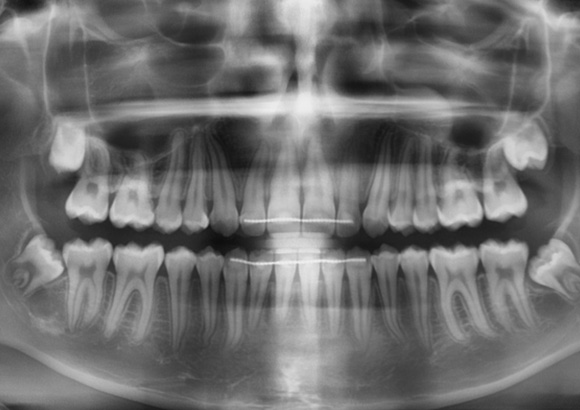

A 14-year-old male patient presented with a Class II sub-division 2 malocclusion with significant maxillary and mandibular crowding. The facial profile was convex with a slightly retrusive mandible, tendency to deep bite. Normal upper and lower first incisor inclination was measured, protruded upper and lower lip were noted. A constricted arch form with tapered buccal segments resulted in poor smile width and dark buccal corridors. Along with a reverse smile arc due to insufficient incisor eruption, this resulted in poor smile aesthetics.

The objectives were to create space while maintaining maxillary incisor position, improve the smile arc by erupting incisors, and develop the posterior segments for increased arch length, as well as improved smile width. Resolving crowding through arch development with proper torque control was a key objective, since incisor advancement and increased angulation would damage smile aesthetic and would result in a more pronounced lip. A non-extraction plan was chosen using Damon Ultima PSL System with Ultima wires, along with the use of anterior bite turbos and light elastics for early deep bite and Class II correction.

Variable torque Damon Ultima brackets were chosen for this case. Neutral torque on U2-2 & L1 & L3, proclined torque on U3, retroclined torque on L2 due to crowding and objective of torque control. All permanent teeth were bonded, the bite was disarticulated. The U2-2 brackets were positioned vertically higher to improve the smile arc.

During this phase, the wires were changed to 0.018 x 0.0275 CuNiTi Ultima U/L. Tie-back elastic used between 6s and crimpable hooks to avoid space opening and the elastics were changed to night-time vertical frontal elastics to help with the eruption of the maxillary incisors. For this, the anterior bite turbos were removed and the disarticulation was moved to the posterior area, on U7s. A few brackets were repositioned after panoramic x-ray control.